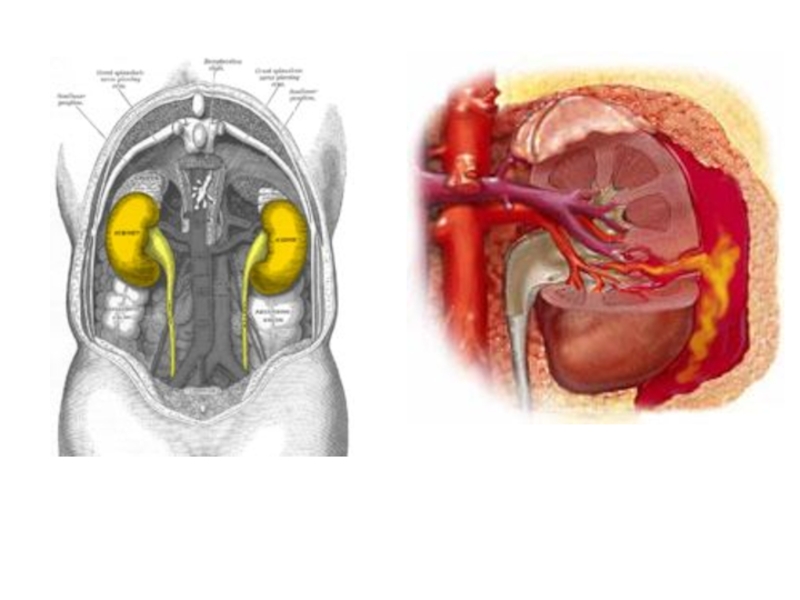

Повреждения почки

Принято различать закрытые и открытые повреждения по­чек.

Открытые повреждения — чаще всего огнестрельные ра­нения.

Причиной закрытых повреждений почек являются прямой удар в поясничную область, падение на твердый предмет, сдавливание, ушиб всего тела.

По виду повреждения делятся на:

ушибы почек,

разрывы паренхимы почки,

размозжение почки,

повреждение сосудистой ножки.

Для закрытой травмы почек характерна триада клинических симптомов: боль в поясничной области, припухлость почечной области (околопочечная гематома, урогематома), гематурия